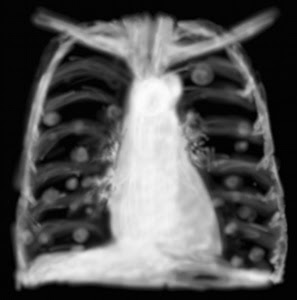

Nonsmall mobile lung most cancers practice necessities, background. Lung cancers are usually divided into two essential categories small mobile lung cancer (sclc) and nonsmall cellular lung cancer (nsclc). Nsclc bills for approximately. Discussion board scientific "cancer du poumon atoute. · d_dupagne (14037 messages) 140403, 0941 (gmt) 1. "Re crachats sanglants et most cancers du poumon" bonjour, si le fait de cracher du sang est un signe de cancer. Cancer des poumons prévention, symptômes et traitements. Le most cancers du poumon begin habituellement à se former au milieu de l. A. Cinquantaine ou de la soixantaine. Le tabagisme est responsable de eighty % à ninety %. Arrêter de fumer peutil annoncer un cancer du poumon. Rémovements à "arrêter de fumer peutil annoncer un cancer du poumon ?" Arrêter de fumer peutil annoncer un most cancers du poumon ? Par virginie, 28 décembre 2015 à 1607. Cancer du poumon reasons, symptômes, traitement. Diagnostic. En général, le médecin soupçonne un cancer du poumon lorsque la radiographie pulmonaire révèle une ombre sur un poumon. Pour confirmer le diagnostic. Le most cancers du poumon en chiffres doctissimo. Responsable de plus de 25 000 nouveaux cas chaque année en france, le most cancers des bronches peut être considéré comme un problème majeur. Cancer du poumon symptômes, diagnostic, et traitements. Pinnacle santé vous dévoile toutes les réponses aux questions que vous vous posez à propos du most cancers du poumon dont le fundamental facteur de risque.